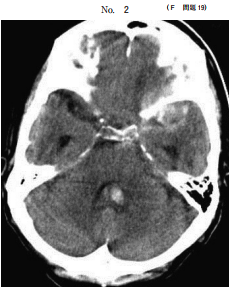

19 50 歳の女性。頭痛を主訴に来院した。日前の夕食中に突然の頭痛を自覚した。 翌日も頭痛は続き、37.8 ℃の発熱もあったため、自宅近くの診療所を受診した。 鎮痛薬を処方され内服したが、頭痛が改善しないため救急外来を受診した。意識は 清 明。身 長 156 cm、体 重 57 kg。体 温 36.8 ℃。脈 拍 84/分、整。血 圧 126/70 mmHg。神経学的診察で脳神経に異常を認めない。項部硬直と Kernig 徴候とを認 めない。四肢の運動系に異常を認めず、腱反射は正常で Babinski 徴候を認めない。 血液所見と血液生化学所見とに異常を認めない。頭部単純 CT8別冊No. 2:を別に 示す。 対応として適切なのはどれか。

(A) 経過観察 (B) 腰椎 刺 (C) 止血薬静注 (D) 降圧薬内服 (E) 頭部 CT 血管造影検査